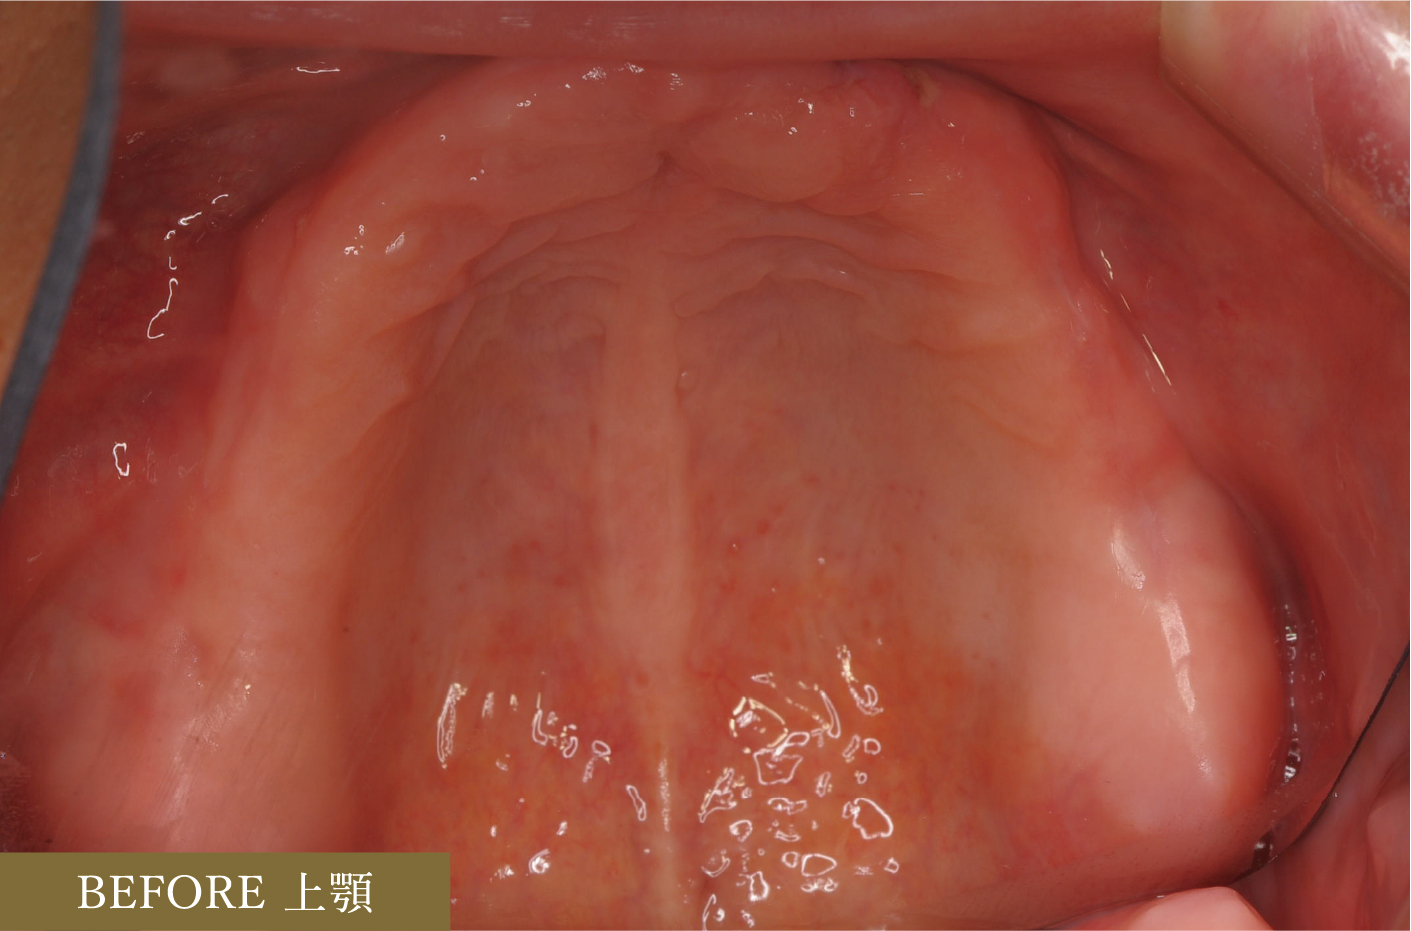

■術前術後の口腔内写真(義歯有)

■治療前後の口腔内写真

上顎では左上3以外すべての歯に根管治療を行いました。

左上7にはソフトアタッチメント、左上4・右上5,7にはコーピング(歯に装着する金属のキャップ)、左上1,2,3・右上1にはレスト(義歯の沈下を防ぐための維持装置)を用いてスマートデンチャーを作成。